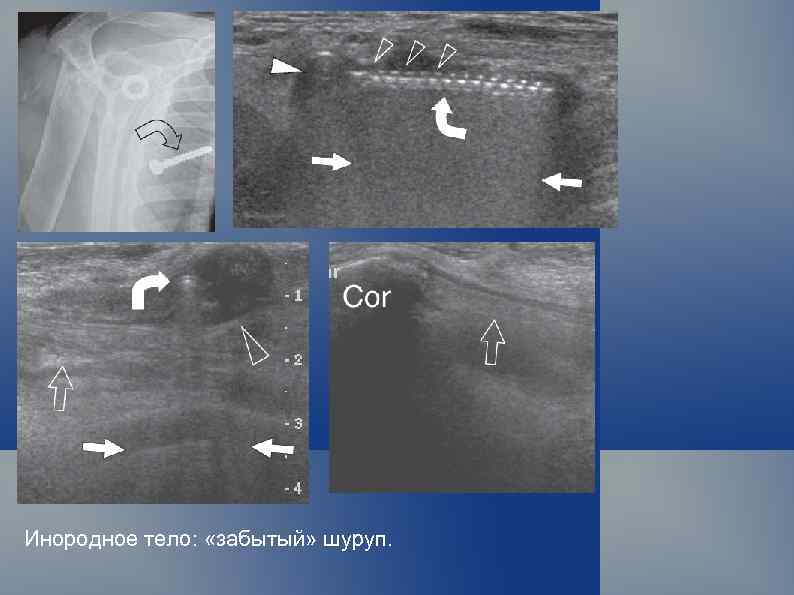

Инородное тело: «забытый» шуруп.